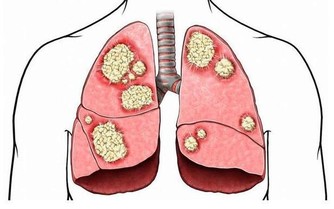

肥胖、“三高”、心血管疾病、老年癡呆、頸椎病、糖尿病、乳腺癌和結腸癌等慢性疾病被認為與缺乏運動有關。而體能運動不足已經成為繼吸煙、過量攝入酒精、不健康飲食後第四大導致人類早死的原因。據統計,全球每年因運動不足造成的死亡人數高達530萬。

以心腦血管為例,長期缺乏運動,心臟泵血量下降,血液中多餘的脂肪、膽固醇、糖分等無法排出囤積在血液裡,造成血液濃稠易在血管中形成粥樣硬化斑塊、血栓等。隨年齡增長,心梗、腦梗和腦出血等疾病風險增加。